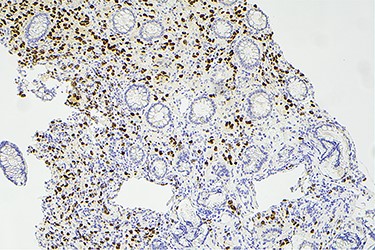

Surveillance colonoscopy in 2018 identified a fungating nonobstructing mass in the sigmoid colon (Fig. 1). Histology from a biopsy showed poorly differentiated carcinoma (Fig. 2). Given the history of breast cancer, further immunohistochemical staining was performed, which was positive for E-cadherin (Fig. 3), ER (Fig. 4), PR, GATA3 binding protein (GATA 3) (Fig. 5) and negative for Cytokeratin 20 (CK20) (Fig. 6). This confirmed metastatic invasive ductal carcinoma of breast. A positron emission tomography (PET) scan showed only the retroperitoneal mass involving the proximal sigmoid colon with no other evidence of metastatic disease (Fig. 7).

Histology slide showing positive immunohistochemical staining for GATA receptor.

Histological examination often involves multiple markers to further assist in the diagnosis. According to the literature, helpful markers include GCDFP-15, ER, PR and GATA-3 [5, 9]. Expression of CK-7 and absence of CK-20 is also commonly seen in ductal carcinoma [10]. The immunohistochemical profile for our case was positive for E-cadherin, CK-7, ER, GATA-3 and negative for CK-20 and CDX2.